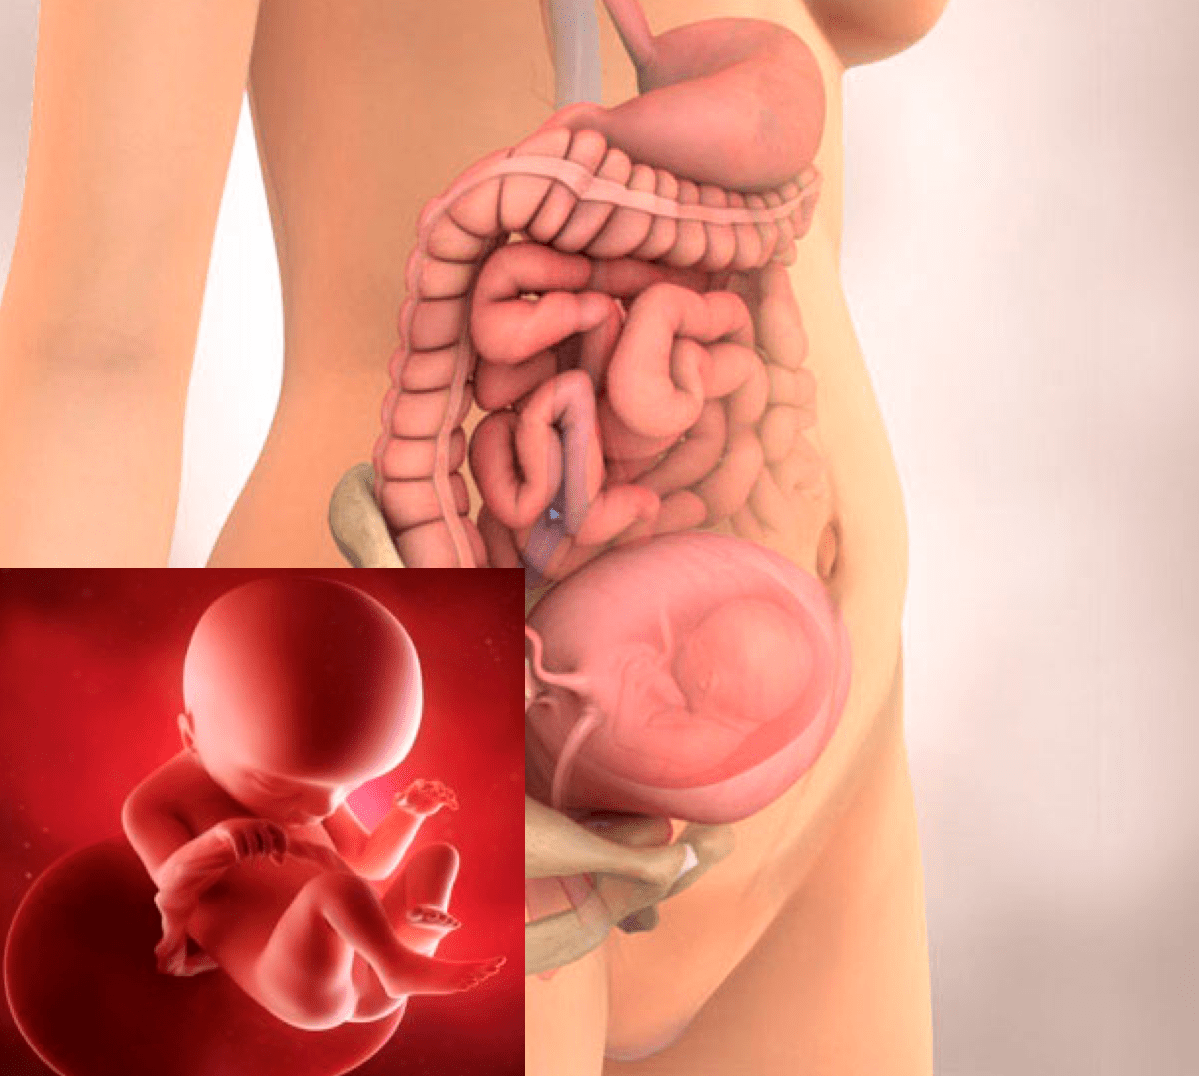

16-17 недель беременности: развитие малыша